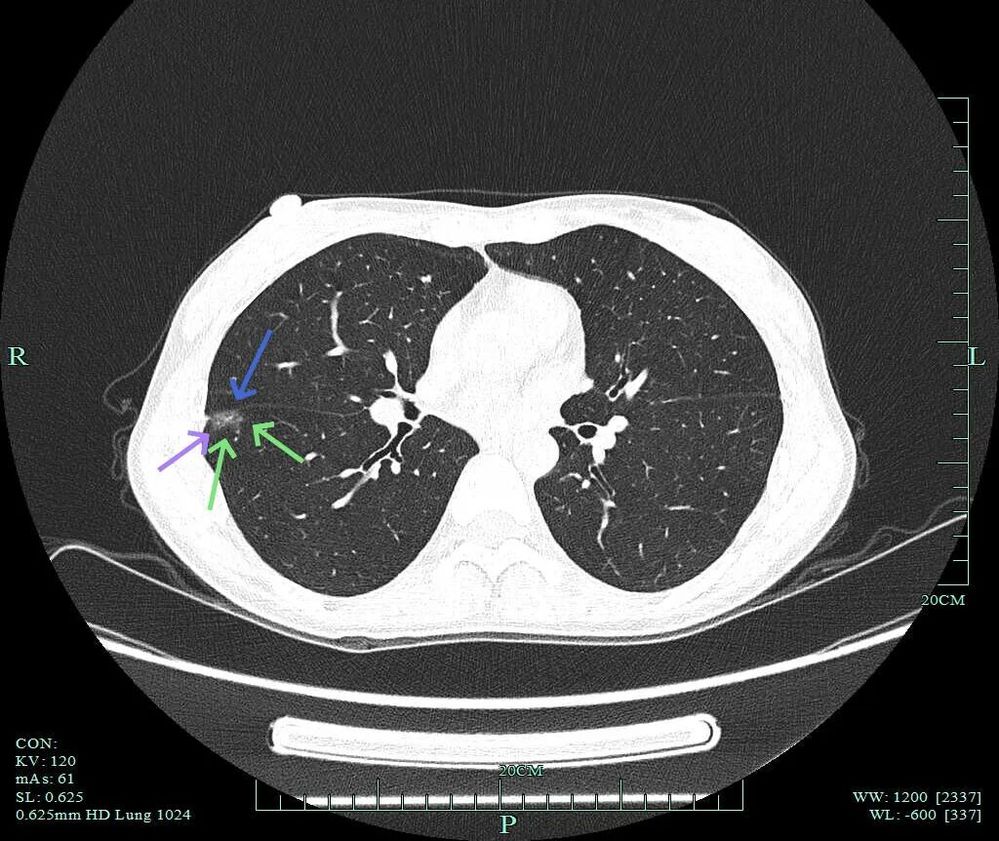

非薄层上右下主病灶A有微小血管进入,距离胸膜近,表面不平,灶内密度稍不均。

薄层上病灶出现,靠叶间裂处密度高呈实性成分,边上是磨玻璃成分,轮廓较清。